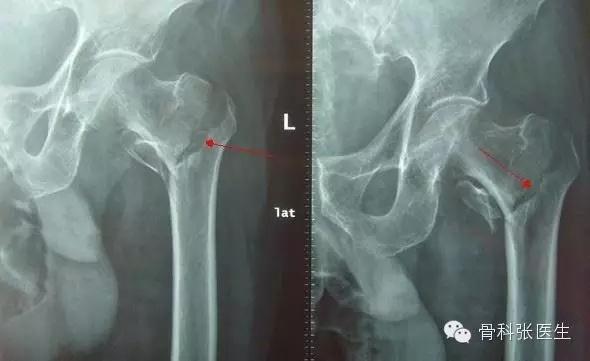

髋部摄片示粗隆间骨折II型(Evans分型)

受伤后,粗隆区出现疼痛、肿胀、瘀斑和下肢不能活动。检查发现粗隆间压痛,下肢外旋畸形明显,可达90°,有轴向叩击痛。测量可发现下肢短缩。X摄片可明确骨折的类型及移位情况。